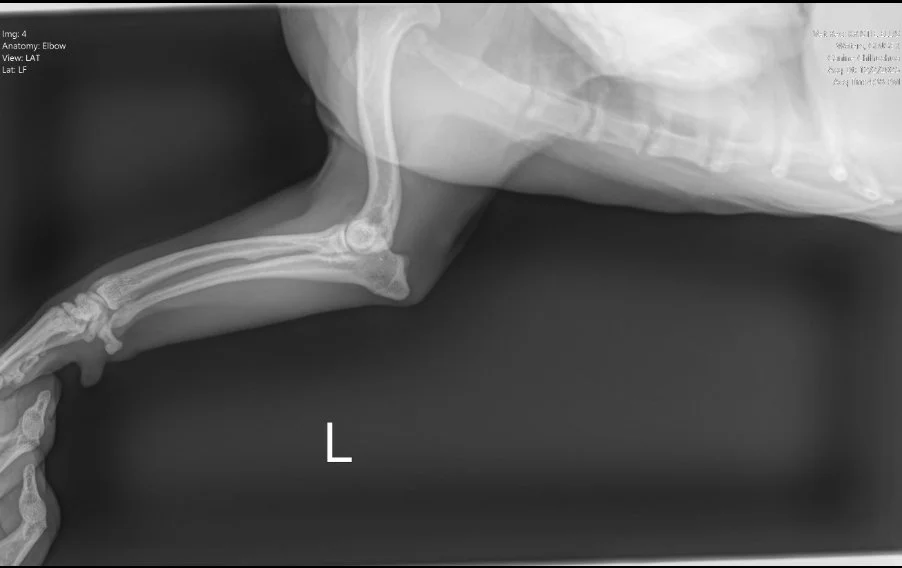

Image 2. Lateral radiograph of the left forelimb.

Lateral radiograph of the left elbow and antebrachium in a dog with no evidence of fracture or bone lysis

Radiographs (Images 1–4) of the left forelimb, including the carpus, elbow, and shoulder identified:

• Mild degenerative joint disease (arthritis)

• Decreased shoulder joint space

• No fractures, masses, or bone lysis

Based on these findings, Ginger was treated for osteoarthritis. However, her clinical progression did not match the imaging results.